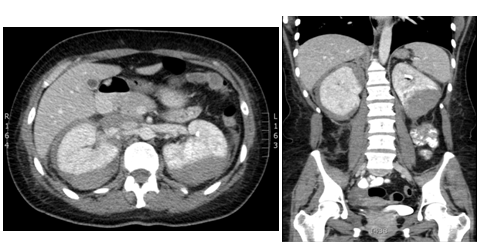

An unclear picture led to a CT pulmonary angiogram, which did not reveala pulmonary embolism but it was incidentally found that there were bilateral large renal haematomas (Figure 1). Subsequent blood tests revealed worsening renal function, inflammatory markers, and anaemia requiring blood transfusions. The patient was also found to be ANCA positive with a raised MPO titre of 134U/ml. A renal angiogram was performed and showed several renal artery aneurysms (Figure 2).

Figure 2 Renal angiogram right and left showing extensive renal artery aneurysms, with compression of left renal artery as a result of the haematoma.